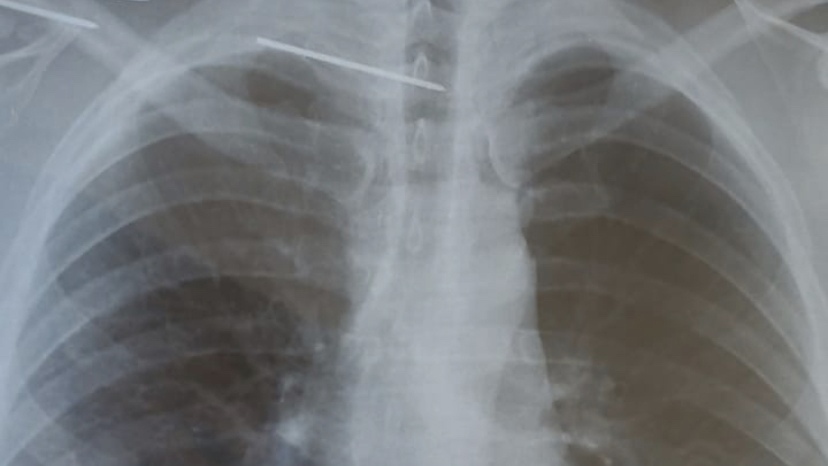

«В ОКБ поступил мужчина со спицей в позвоночнике, – рассказал главврач ОКБ. – Придумать случай сложнее было бы невозможно – спица прошла через сосудистый нервный пучок, пересекла грудной отдел позвоночника и проткнула спинной мозг. Следствием стало онемение ног у пациента, с жалобой на которое он и обратился в нейрохирургическое отделение ОКБ».

После всех диагностических процедур выяснилось, что спица попала в позвоночник пациента после операции в одной из клиник. Этой спицей мужчине скрепили ключицу, чтобы вылечить перелом. Далее, по необъяснимым причинам, она откололась, проникла в позвоночник и могла спровоцировать гнойно-септическое осложнение. Требовалась срочная операция. При этом оставался высоким риск, что мужчина останется парализованным. Поврежденный спинной мозг мог перестать проводить импульсы от головного мозга к конечностям.

«Я уверен, что хирургическое лечение завершилось успешно благодаря тому, что все наши специалисты сработали профессионально и слаженно, – продолжил Андрей Карпунин. – Пока хирурги аккуратно продвигались через ткани, чтобы достичь инородного тела, анестезиологическая бригада поддерживала показатели пациента. Особенно сложным был этап извлечения спицы. Требовалась ювелирная работа, чтобы не повредить тонкие структуры спинного мозга».

Фото: Андрей Карпунин, ВКонтакте.